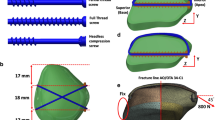

The inferior pole patellar fracture line was created. CSTBW and DSTBW surgical procedures were applied to fix the fracture by ProE 5.0 software (PTC Inc., Boston, MA). In the CSTBW group (Fig. 2a); fractures were fixed using traditional methods, as described in previous studies [9]. In the DSTBW group (Fig. 2b), the fracture was fixed according to the method described in our previous study [9].

Finite element analysis: displacement of fractures

In a neutral loading of 400 N, there was less displacement of DSTBW in different knee movement (30°, 60°, 90°, 120°) when compared to CSTBW(Table 2). The highest displacement of the fractured patella happened in 120° knee movement in both CSTBW and DSTBW group, the relative displacement was as follows: 2.12 mm for the CSTBW (Fig. 3a); 1.92 mm for the DSTBW (Fig. 3b).

Finite element analysis: von Mises stress on fixation

There was no fixation failure in either fixation system. There was less stress distribution of DSTBW in different knee movement (30°, 60°, 90°, 120°) when compared to CSTBW (Table 3).The highest value of von Mises stress of the femur, platella, screw and titanium cable happened in 120° knee movement in both CSTBW (Fig. 4) and DSTBW group (Fig. 5). The highest value of the stress on the screws was 110.60 MPa in DSTBW group and 132.90 MPa in CSTBW group. The highest value of the stress on the titanium cable was 38.51 MPa in DSTBW group, and 41.91 MPa in CSTBW group. The highest value of the stress on the patella was 9.75 MPa in DSTBW group, and 11.88 MPa in CSTBW group.